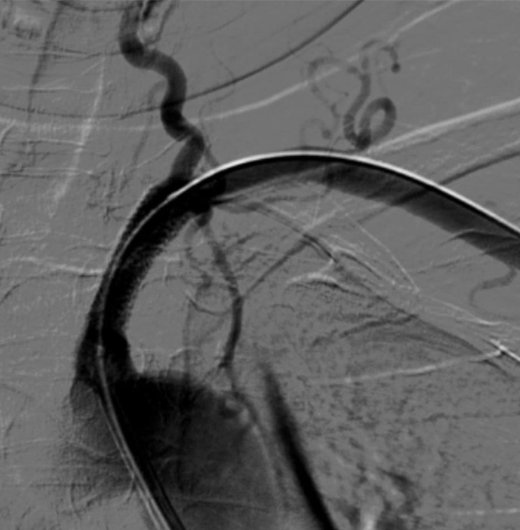

MRI/CT interpretation and Thrombectomy and stenting/ plasty for acute and recurrent stroke. Cerebral DSA

Thrombectomy – mechanical , pharmacological and combined therapy for acute stroke.